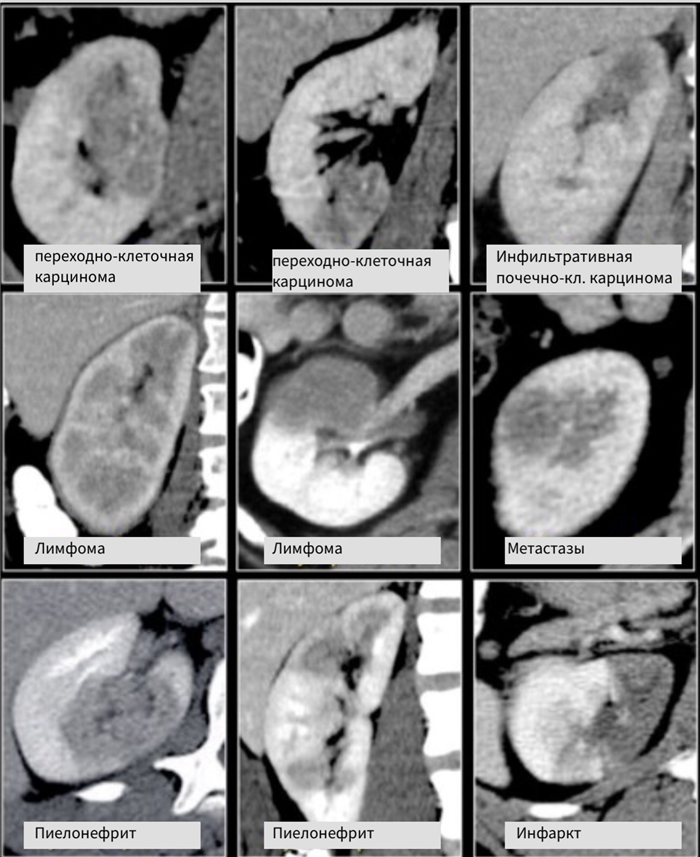

Радиологические признаки образований бобовидной формы обычно не специфичны. Данное явление заметно если обратить внимание на схожесть образований, представленных на рисунке. Дифференциальный диагноз обычно строят, исходя из клинических данных и, соответственно, данных визуализации.

Инфильтрирующее почку по центру образование у пожилого пациента соответствует переходно-клеточному раку почки. Инфильтрирующее почку по центру образование у молодого пациента с серповидной перегородкой внутри больше соответствует медуллярной карциноме почки. Мультифокальные и билатеральные или диффузные образования почки в сочетании с лимфоаденопатией, а также с вовлечением в патологический процесс других органов характерны для лимфомы.

Мультифокальные и двусторонние поражения почек характерны для злокачественных образований, в частности для метастазирования. У пациентов с клиникой характерной при инфекции, конечно же, в первую очередь нужно подозревать пиелонефрит. Для инфаркта почки характерно клиновидное поражение почки.